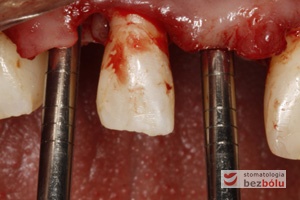

Proces implantacji – pierwsze wiertło pilotowe Lindemana pozwala ocenić gęstość kości i wyznaczyć pozycję implantu

Ustalenie pozycji implantu – wiertło Lindemana wyznacza nachylenie i oś długą dla wprowadzanego implantu

Ocena pozycji implantów w wymiarze strzałkowym – piny do oceny równoległości wprowadzone do łoży implantów – widok okluzyjny